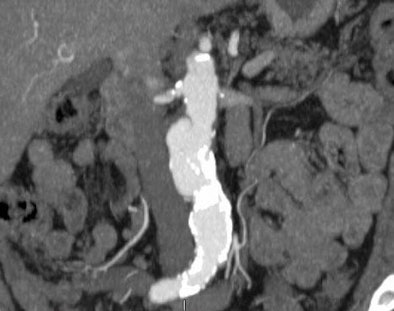

At index CTC, AAA was detected in 0.8% of the patients (9/1,061; 95% confidence interval: 0.4%-1.6%), with a mean diameter of 3.10 ± 0.2 cm. Additional abdominal vascular aneurysms (n = 5) included common iliac artery (n = 3), femoral artery (n = 1), and splenic arteries (n = 1), for an overall prevalence of 1.3% (14/1,061).

![]() |

| Abdominal aortic aneurysm detected at CTC screening. Image courtesy of Dr. Dustin Pooler. |